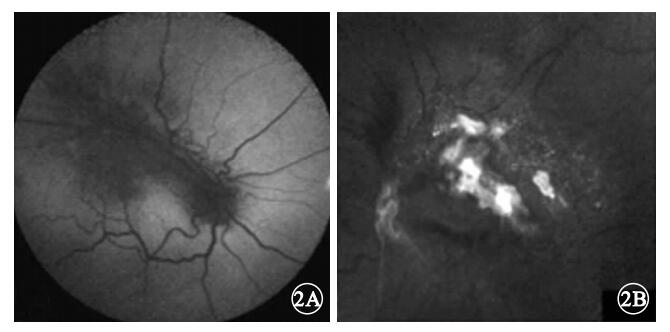

AF檢查發現,8只眼中,病灶隆起處及其周圍色素沉著區域AF亮度降低(圖 2A)7只眼,占87.5%;AF亮度增強部位與病灶表面致密的前膜相對應(圖 2B)1只眼,占12.5%。

AF檢查發現,8只眼中,病灶隆起處及其周圍色素沉著區域AF亮度降低(圖 2A)7只眼,占87.5%;AF亮度增強部位與病灶表面致密的前膜相對應(圖 2B)1只眼,占12.5%。

Font等[2]通過摘除誤診為脈絡膜黑色素瘤的CHRRPE患眼行病理學檢查,發現瘤體內組織層次不清,主要由雜亂的視網膜血管、膠質及增生的RPE細胞構成。不同CHRRPE病灶內膠質或RPE細胞的成份各有不同,可能主要以膠質增生為主,也可能以增生的RPE細胞為主,但血管成份較少。這些增生的RPE細胞可位于外層視網膜,也可位于內層視網膜或瘤體表面[3, 4]。AF圖像能夠顯示RPE內脂褐質的含量與分布,可依此評價RPE的代謝狀況。我們發現,7只眼的CHRRPE病灶及其周圍色素沉著區域AF亮度降低。說明CHRRPE病灶沒有產生AF的物質。而CHRRPE病灶周圍沉著的色素導致其下方RPE因遮蓋也無AF產生。說明CHRRPE病灶周圍色素沉著并非與此區域RPE細胞異常增生有關,這些色素的來源仍待研究。但根據AF亮度降低的范圍可判斷CHRRPE病灶及其周圍色素沉著的面積。我們還發現,1只眼的病變部位有局灶性AF亮度增強表現,其分布與CHRRPE病灶表面致密的纖維膜相對應。我們認為這可能與致密纖維膜對激發光的強反射有關。

Font等[2]通過摘除誤診為脈絡膜黑色素瘤的CHRRPE患眼行病理學檢查,發現瘤體內組織層次不清,主要由雜亂的視網膜血管、膠質及增生的RPE細胞構成。不同CHRRPE病灶內膠質或RPE細胞的成份各有不同,可能主要以膠質增生為主,也可能以增生的RPE細胞為主,但血管成份較少。這些增生的RPE細胞可位于外層視網膜,也可位于內層視網膜或瘤體表面[3, 4]。AF圖像能夠顯示RPE內脂褐質的含量與分布,可依此評價RPE的代謝狀況。我們發現,7只眼的CHRRPE病灶及其周圍色素沉著區域AF亮度降低。說明CHRRPE病灶沒有產生AF的物質。而CHRRPE病灶周圍沉著的色素導致其下方RPE因遮蓋也無AF產生。說明CHRRPE病灶周圍色素沉著并非與此區域RPE細胞異常增生有關,這些色素的來源仍待研究。但根據AF亮度降低的范圍可判斷CHRRPE病灶及其周圍色素沉著的面積。我們還發現,1只眼的病變部位有局灶性AF亮度增強表現,其分布與CHRRPE病灶表面致密的纖維膜相對應。我們認為這可能與致密纖維膜對激發光的強反射有關。